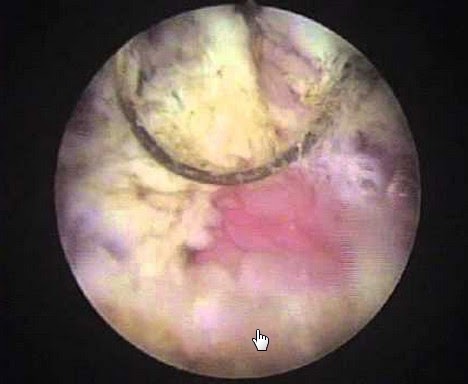

La cistoscopia debe realizarse siempre bajo sedación o anestesia general, pues debe realizarse hidrodistensión vesical en busca de signos de cistitis intersticial.

Es frecuente encontrar en estas pacientes alteraciones en el trígono conocidas como trigonitis.

Cirugía de cauterización

No existen a la fecha estudios suficientes que demuestren que la cirugía de cauterización del trígono, sea eléctrica o láser, mejoren el cuadro clínico.

La respuesta clínica favorable luego de la cirugía de algunos pacientes puede deberse a la necrosis del epitelio metaplásico el cual es reemplazado por tejido urotelial.